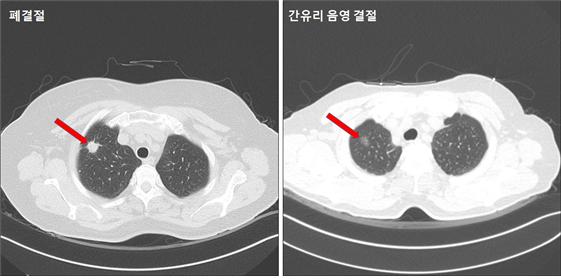

위의 사진에서 보시는 바와 같이 왼쪽의 폐결절은 원형의 선명한 하얀색인데 반해 오른쪽의 간유리음영 결절의 경우에는 회색빛으로 명확하게 보이지 않습니다. 음영이 더 진해지는지 커지는지는 관찰이 필요한 상태입니다.